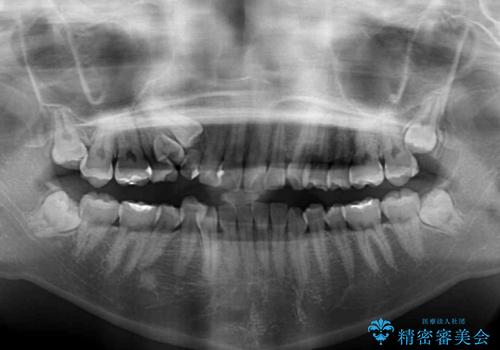

- 前歯のでこぼこと乳歯が残るほどの八重歯を気にして来院された患者様です。

非抜歯にてワイヤー矯正にて治療することとしました。(ただし、親知らずと乳歯は抜歯)

犬歯は歯根が太く長いため、移動には時間を要します。しかし、犬歯は機能面から考えて残すことを選択したいため、長期間をかけて治療を行うこととしました。